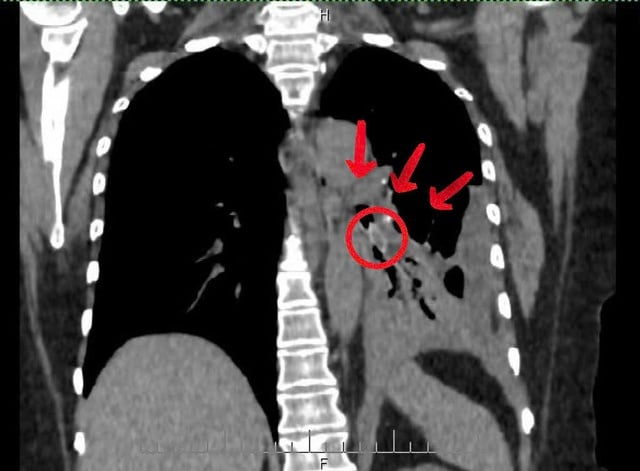

Ca thứ nhất là ông V.T.Đ. (65 tuổi, phường Quỳnh Mai, Nghệ An) nhập viện ngày 22/11 trong tình trạng khó thở, đau ngực trái. Kết quả chụp cắt lớp cho thấy có dị vật sâu trong đường thở. Ê - kíp cấp cứu phối hợp bác sĩ nội soi tiến hành can thiệp khẩn.

Qua nội soi phế quản, bác sĩ phát hiện một hạt hồng xiêm trơn bóng mắc tại phế quản phân thùy 4 - 5 trái, gây viêm mạnh và nhiều mủ trắng che kín lòng phế quản. Sau gần 30 phút thao tác tỉ mỉ, dị vật dài khoảng 2 cm đã được gắp ra an toàn.